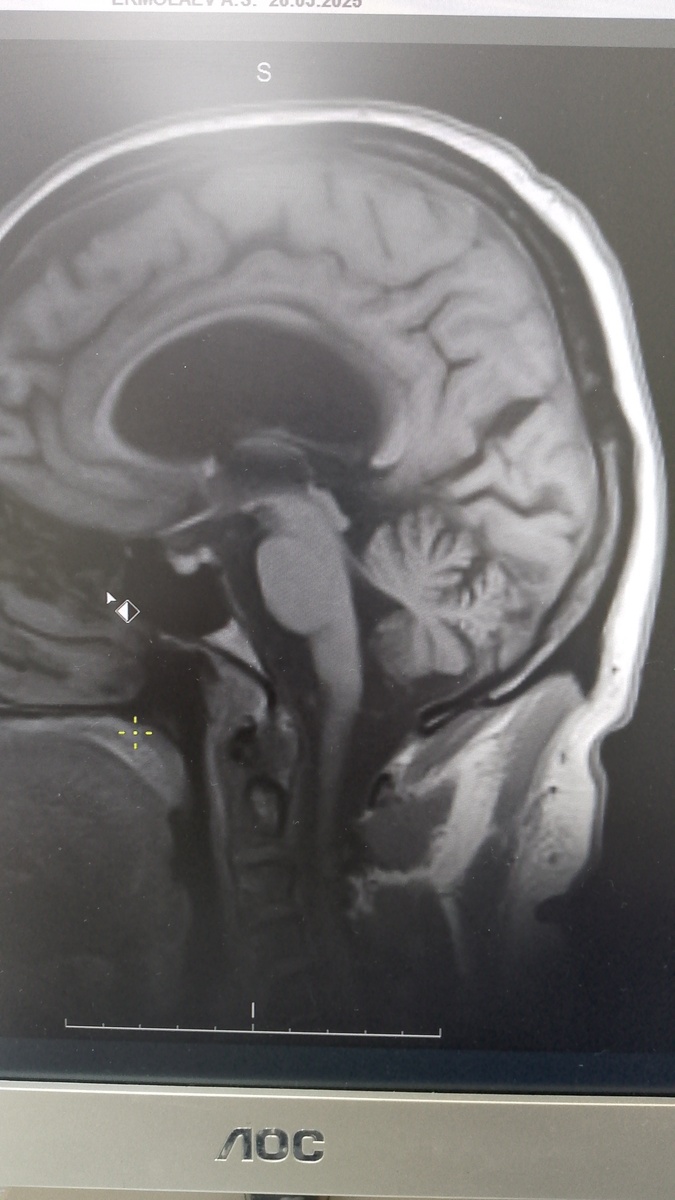

В феврале у меня были трое пациентов 50+, у которых это все было + у кого то были иные жалобы, но течение их заболевания не было похоже на выше описанное ПППГ и причина была другая- дегенеративное заболевание головного мозга. Это группа заболеваний с прогрессирующим течением, построенным нарастанием симптомов

Но есть отдельная группа неврологических заболеваний - дегенеративные заболевания нервной системы. Начало может быть с такими симптомами, но с особенностями, иногда, яркими, а иногда менее заметными